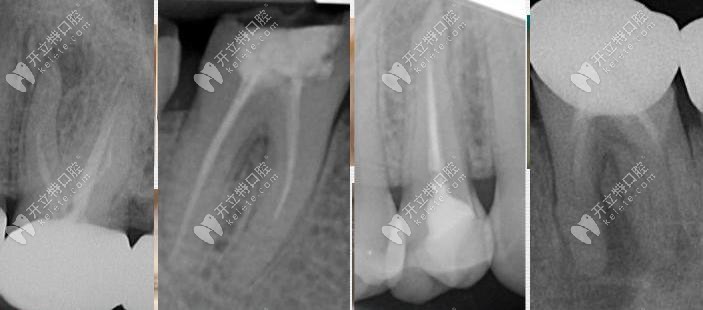

根管治療修復(fù)顯微根管治療發(fā)布時(shí)間: 2025-04-25

你是否也有寧愿拔牙也不做根管治療的想法呢?如果有的話,也是對(duì)的,畢竟根管治療上雖然可以保留部分牙根,對(duì)于醫(yī)生的操作要求也比較高。所以做根管治療后必要注意這幾大不成功表現(xiàn)。